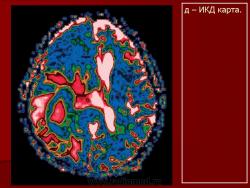

Лимфомы головного мозга.